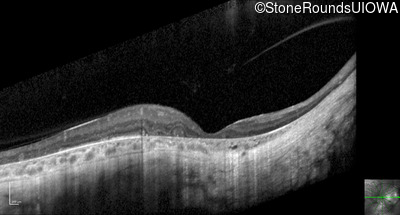

Optical Coherence Tomography - Left - 20/40 sc

Exemplar / OCT Stack